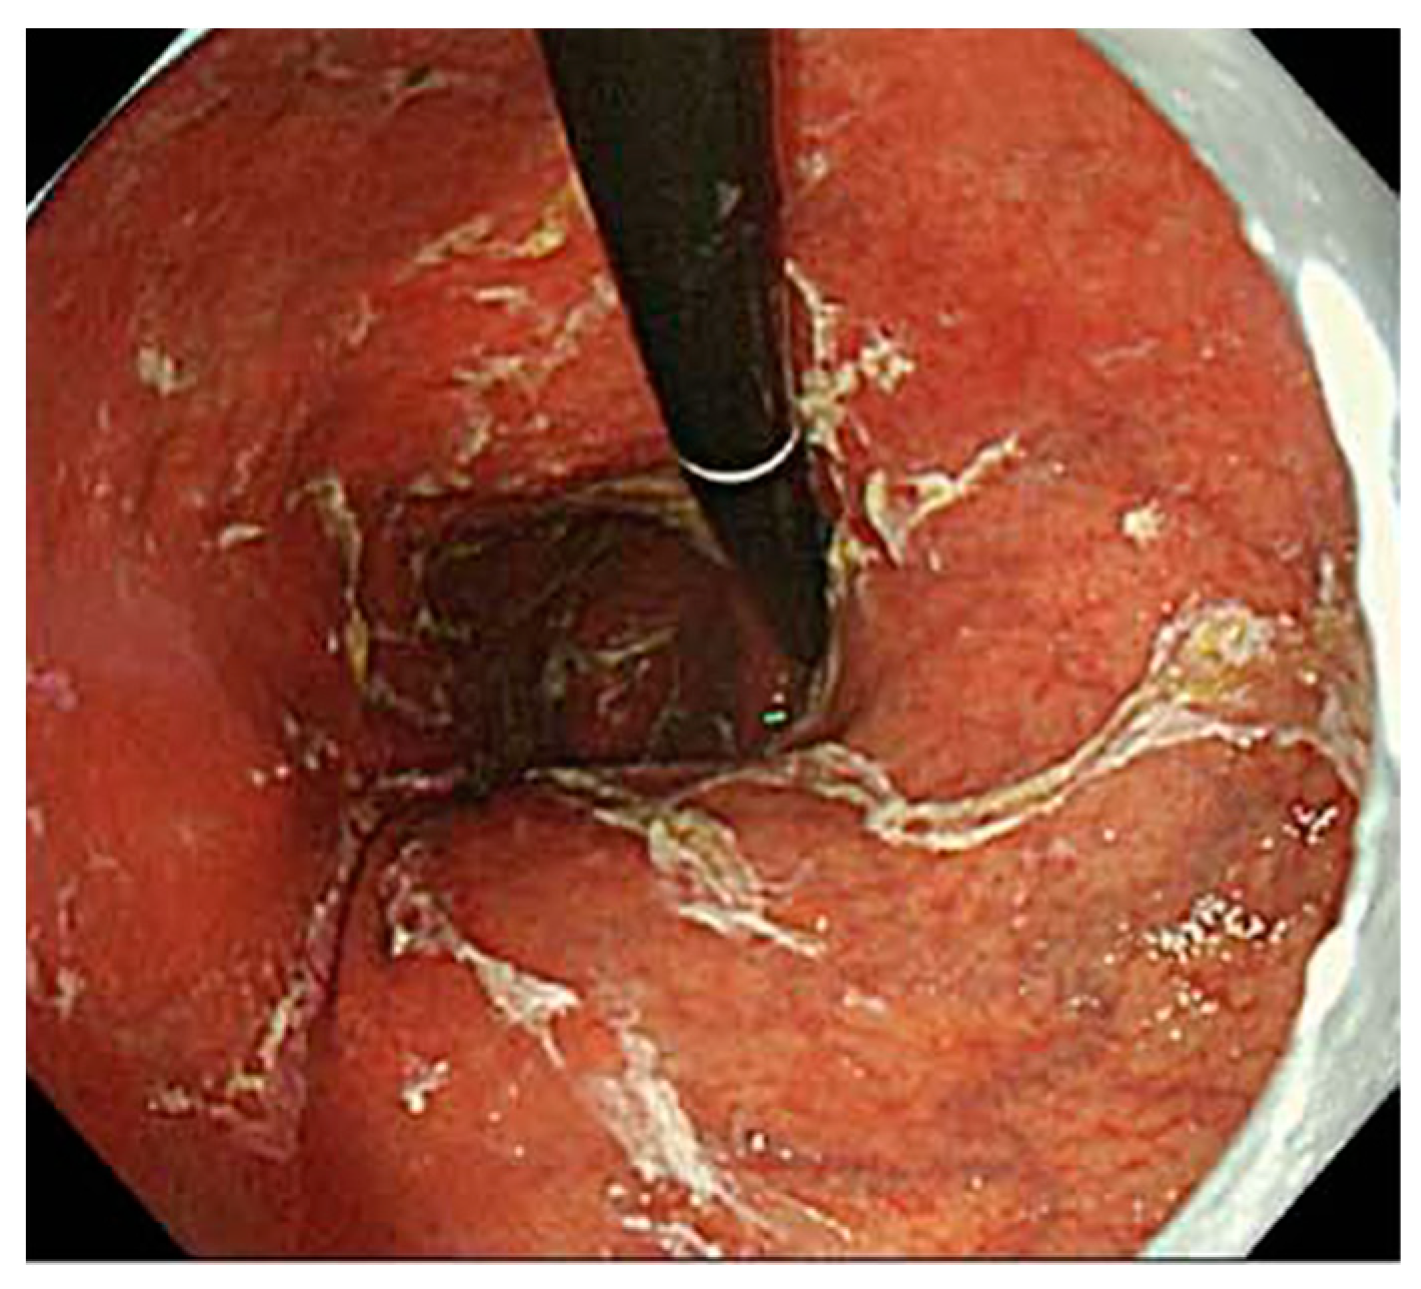

5. Findings of Early AIG

- Kotera, T.; Yamanishi, M.; Kushima, R.; Haruma, K. Early autoimmune gastritis presenting with a normal endoscopic appearance. Clin. J. Gastroenterol. 2022, 15, 547–552. [Google Scholar] [CrossRef]